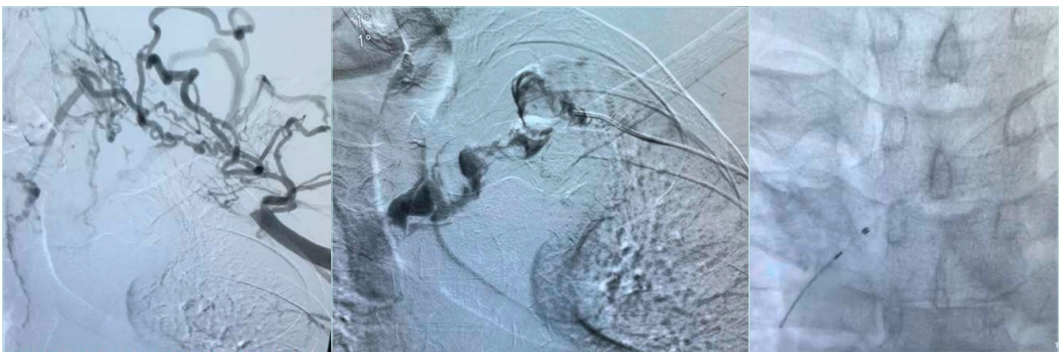

After thrombus removal, immediate completion venography with or without IVUS is recommended to confirm the flow restoration; detect any residual webs, stenosis, or intimal hyperplasia; and to guide decisions about the need for additional decompression or revascularization procedure (Figure 10).

Figure 10. Post-lysis venous stenosis was persistent after balloon venoplasty, treated with venous stent.

Studies show that thrombus removal should be followed by surgical decompression for definitive treatment of VTOS.

The primary 5-year patency of the axillary-subclavian vein in patients who undergo thrombolysis followed by surgical decompression is 84%.15 Thus, there is a growing consensus that early diagnosis and early thrombus removal followed by operative first rib resection (FRR) produces the most desirable long-term outcome. Therefore, an early thrombus removal strategy should always be considered as a temporizing measure that enables definitive decompression.